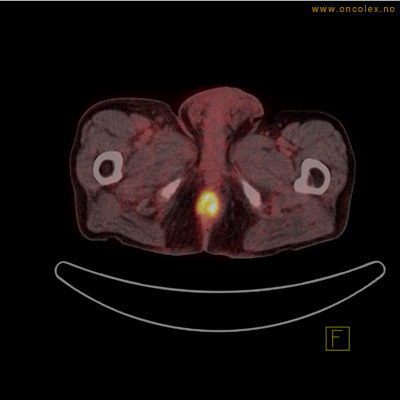

Vev som tar opp mer radioaktivt stoff, synes som hvite områder som lyser opp mer i forhold til annet vev som tar opp mindre sukker.

Høyt opptak av 18F-FDG ved analkreft.